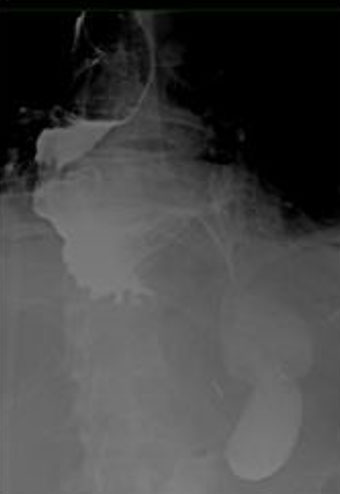

We report the case of a 74-year-old male patient who presented with vomiting, appetite loss, and hematemesis for ten days. A gastroscopy performed two weeks earlier showed grade A esophagitis and a mixed hiatal hernia with sliding and para-esophageal components. We performed another gastroscopy on arrival at the emergency room, which showed grade D esophagitis and a stomach located almost entirely in the thorax. There also was an important alimentary stasis. The CT scan displayed an intra-thoracic stomach positioned on the right side of the chest (Figure 1). From the upper gastrointestinal series, we can clearly see that two-thirds of the stomach are intra-thoracic, with an important dilatation of the esophagus associated (Figure 2). Considering the symptomatology, we decided to perform a laparoscopic hernia repair.

Figure 2: Upper gastrointestinal series with oral intake of contrast, preoperative exam.